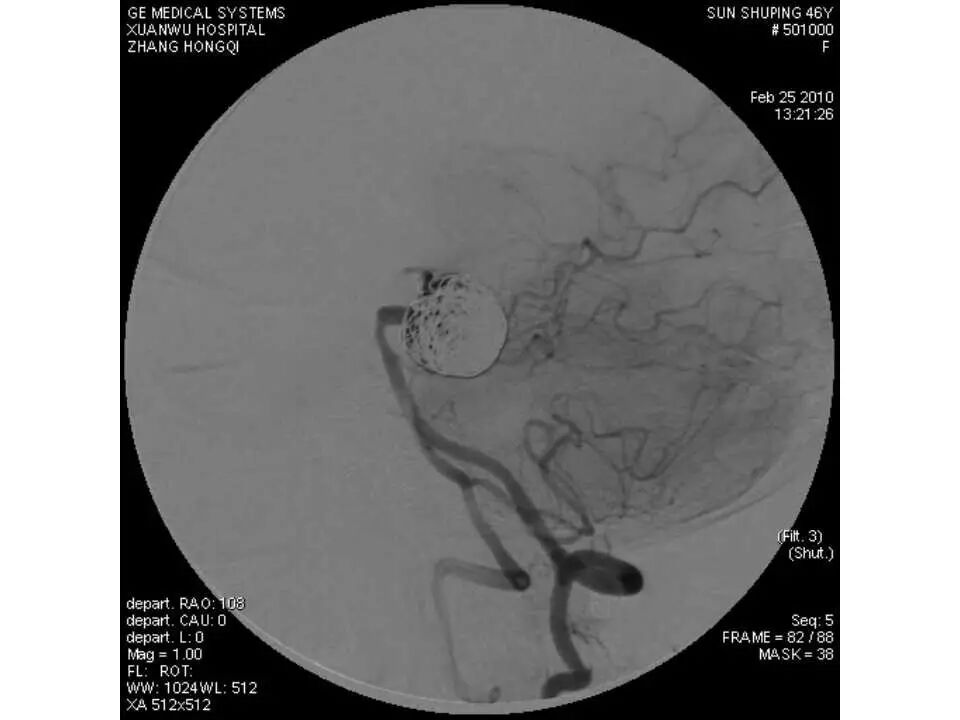

今天为大家分享的是“强生医疗CNV-神经介入专栏”第十五期,由首都医科大学宣武医院何川教授带来的“颅内动脉瘤介入治疗”精彩讲课视频及PPT,欢迎观看、阅读。文章仅代表作者个人观点,如有不同见解,欢迎同道斧正!

何川 ,首都医科大学宣武医院副主任医师,中国医师协会神经介入专业委员会常务委员,长期从事脑血管病和脊髓血管病的手术及介入治疗和相关研究工作。首都医科大学神经外科博士,师从于中国神经介入开创人凌锋教授;日本东北大学医院脑血管病治疗科博士后,师从于日本国脑血管病血管内治疗的开创者高桥教授。